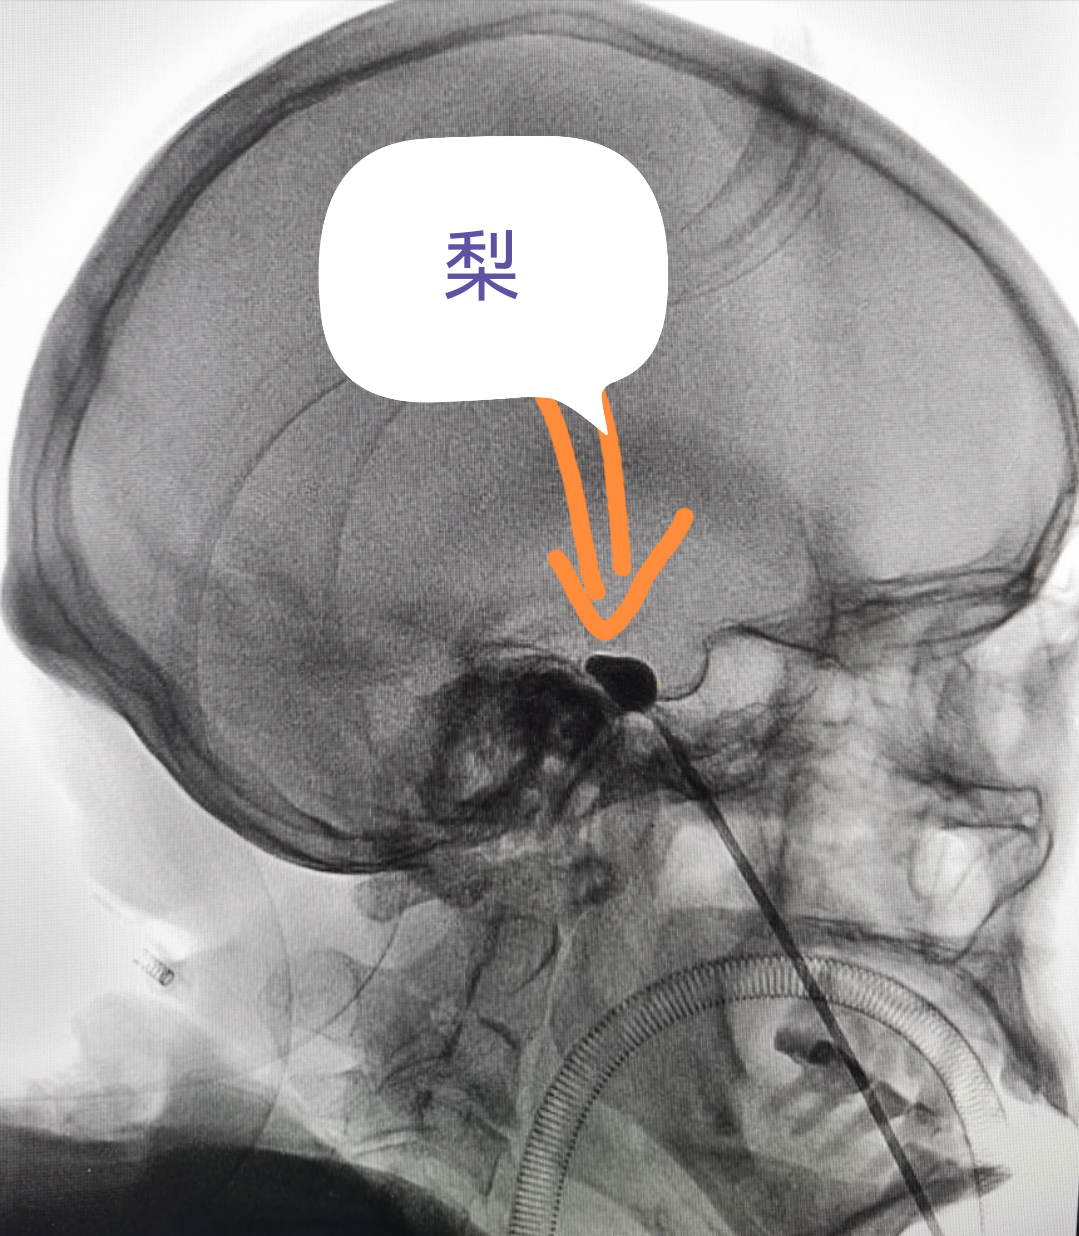

看到这个“梨”,你会想到什么?

治疗三叉神经痛中微创技术在影像上的呈现挺像哒

(看着像梨,哈哈...)

经过面部口角处穿刺到三叉神经半月节内,放入球囊,向球囊里打入对比剂,使球囊扩张,完美显示一个“梨”形,压迫3-5分钟,压迫毁损感觉神经,保留运动神经,阻断疼痛信号传导,达到止痛目的。适合单支或多支发病患者,尤其高龄、合并症多,不愿意接受开颅手术患者。术后面部稍有麻木。